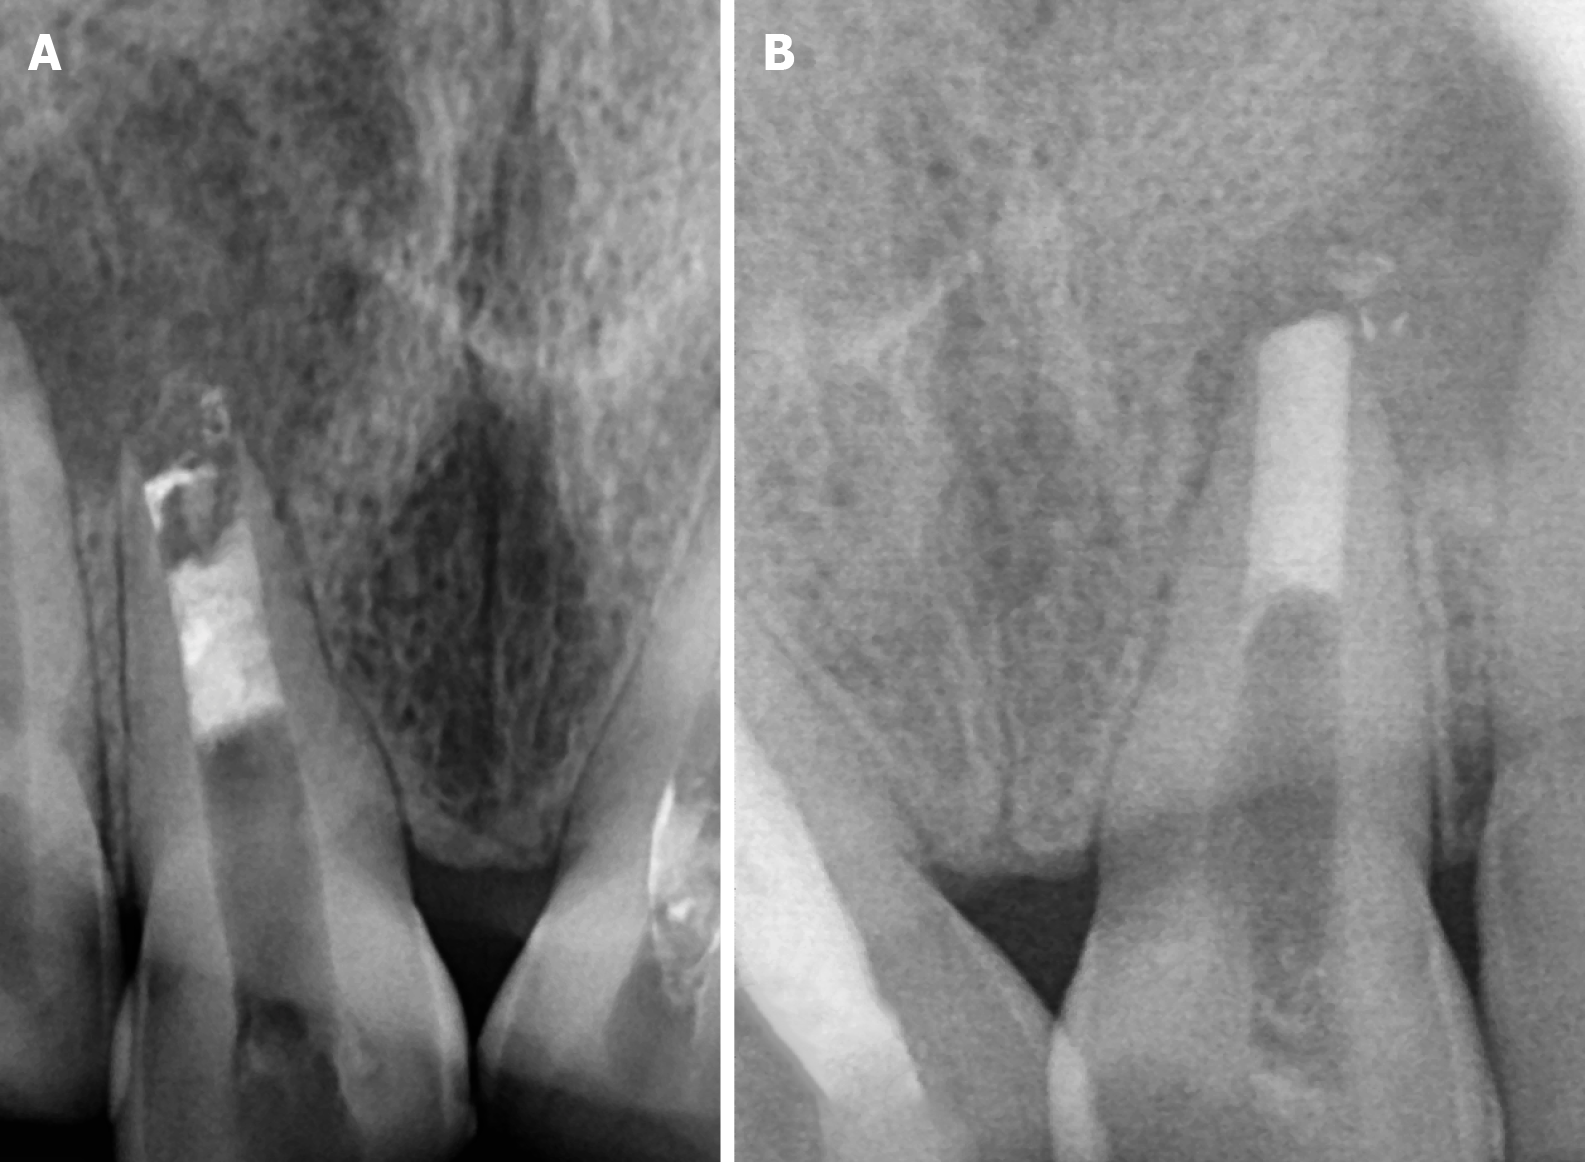

Figure 2 Shows open apex.

A: Wrt 11; B: Wrt 21.